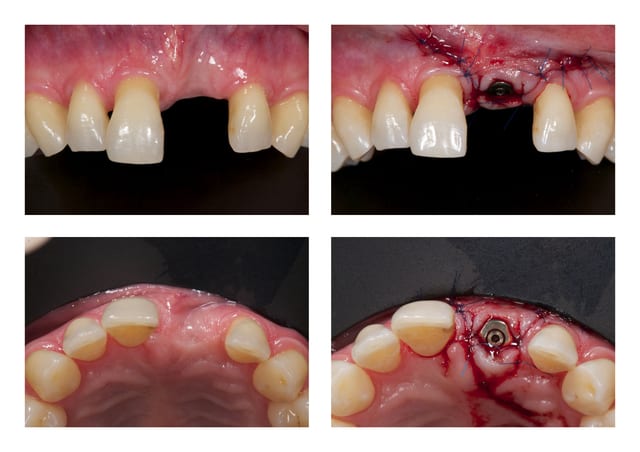

Dsc 5384 jvynur - Eugenol

Q3 df9hw5 - Eugenol

Dsc 6081 qhlsym - Eugenol

Le support paro est stable depuis 3 ans et la maintenance parfaite. je pense ici qu'un traitement ortho serait une bonne solution. j'ai déjà effectué un traitement similaire sur une 12 égressé ( confère photo ci-joint) et même si comme certain l'ont décrit, on a quelques aléas a cette méthode, ca vaut le coup d'essayer.

Merci dancha d'intervenir, j'avoue que j’espérerai bien que ce cas te face sortir de ta tanière et tes conseils sur eugenol m'avaient bien aidé pour réaliser le traitement ci-dessous.